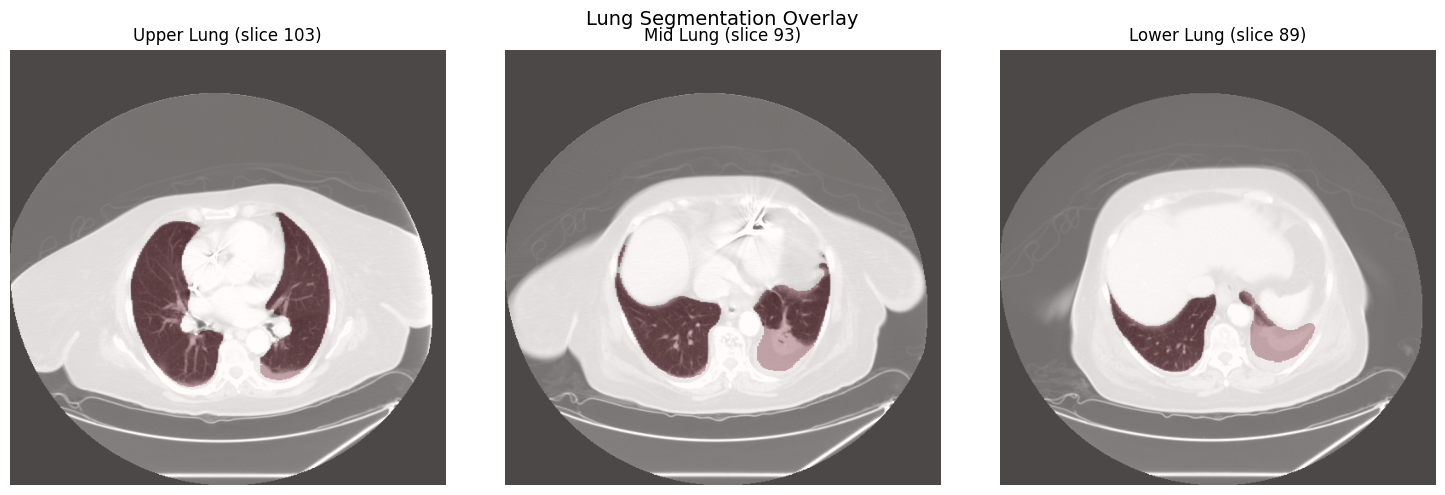

Lung Segmentation

segment_lungs() uses the lungmask library for automatic lung segmentation. The resulting binary mask can be applied with apply_mask() to isolate lung parenchyma before embedding generation.

Lung segmentation overlay on upper, mid, and lower lung zones